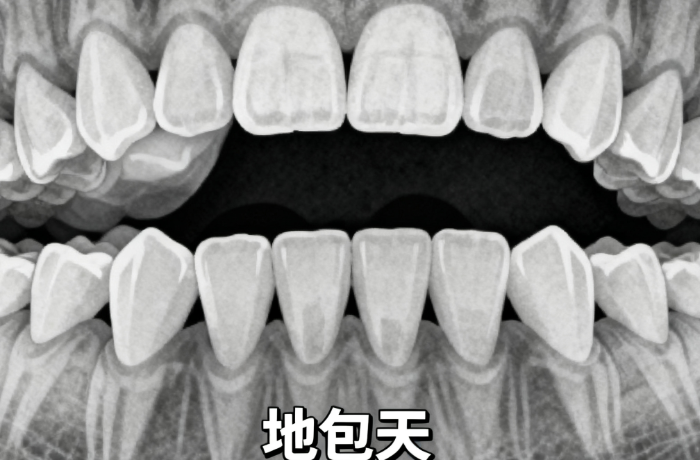

2. 从业经验:从医以来累计完成2000+正畸实例,覆盖青少年早期矫治、成人牙列拥挤、地包天等多种类型,其中不拔牙矫正实例占比超60%,擅长通过稳准评估骨量与牙弓潜力,避免拔牙对牙齿及牙周的损伤。

1. 出诊地点:① 首医附属北京口腔医院正畸科(公办):每周2个半天,处理复杂病例(如地包天、骨性错颌);② 北京禾禾齿科(私立):每周2-3天,侧重私人定制与便捷服务(如周末出诊、一对一沟通)。